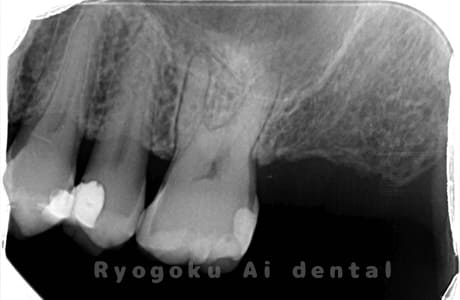

他院で右下の根の治療を行い、セラミックを被せる説明をされていたが、根の治療が終わらないため転院された患者さんです。隣の親知らずの抜歯の必要性と、根の治療を行なっている歯牙の予後が悪いため、移植治療を提案し、右下の親知らずの抜歯と同時に、右下の奥歯(7番)への移植治療を行いました。被せ物を行う必要もなく、順調に経過してます。

<リスク・副作用>

治療後、痛みや違和感、出血、腫れなどが出る事があります。喫煙者、糖尿病などの方の場合、歯が生着しない場合があります。